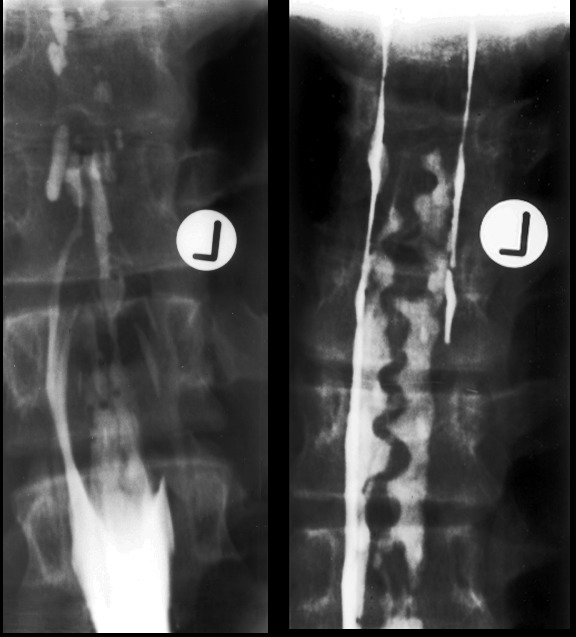

The most favourite subspecialty was angiography and interventional work particularly in the vascular field. This was the first angioplasty performed in the department. This represents atheroma with a focal stricture of the left femoral artery which was dilated with the presented result. Note that the atheromatous process is not limited to one area.

Femoral artery stricture post dilatation. Note the ragged appearance of the dilated atheromatous plaque.